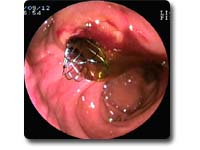

ERCP是将十二指肠镜经口插入十二指肠,寻找十二指肠乳头,再经活检通道置入造影导管并插入乳头,在X线透视下注入造影剂显示胆管、胰管的形态及异常变化。ERCP是胆道和胰腺疾病最为有效的诊断技术之一,也是胆胰疾病内镜下介入治疗的基础。包括:急性化脓性胆管炎、急性胆源性胰腺炎、胆总管结石、胆道蛔虫、梗阻性黄疸术前引流、胆瘘、胰瘘、慢性胰腺炎等。 |